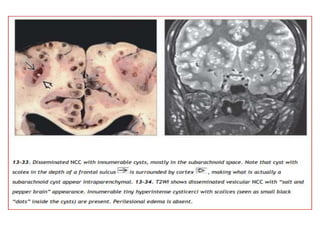

Neurocysticercosis

Cysticercosis is the most common parasitic infection in the world, and

CNS lesions eventually develop in 60-90% of patients with

cysticercosis.